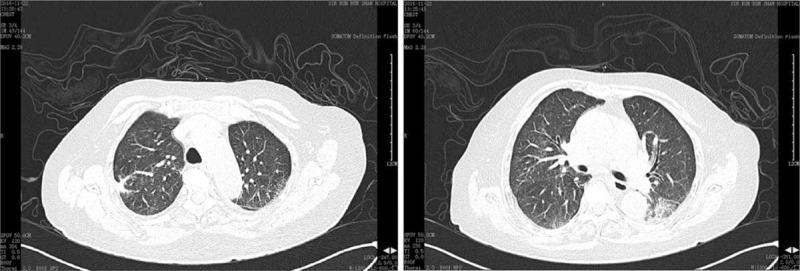

Chest high-resolution computed tomography (HRCT) revealed multiple nodules, masses, and cavities. Urinalysis indicated microscopic hematuria. Test of proteinase3-anti-neutrophil cytoplasmic autoantibody (PR3-ANCA) was positive.

胸部高分辨率计算机断层扫描(HRCT)显示多个结节、肿块和空洞。尿液分析显示镜下血尿。蛋白酶3抗中性粒细胞胞浆自身抗体(PR3-ANCA)检测呈阳性。